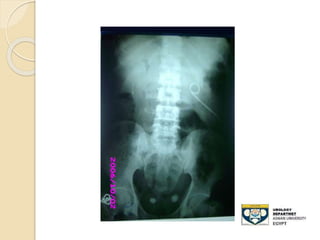

STONE MIDDLE THIRD URETER